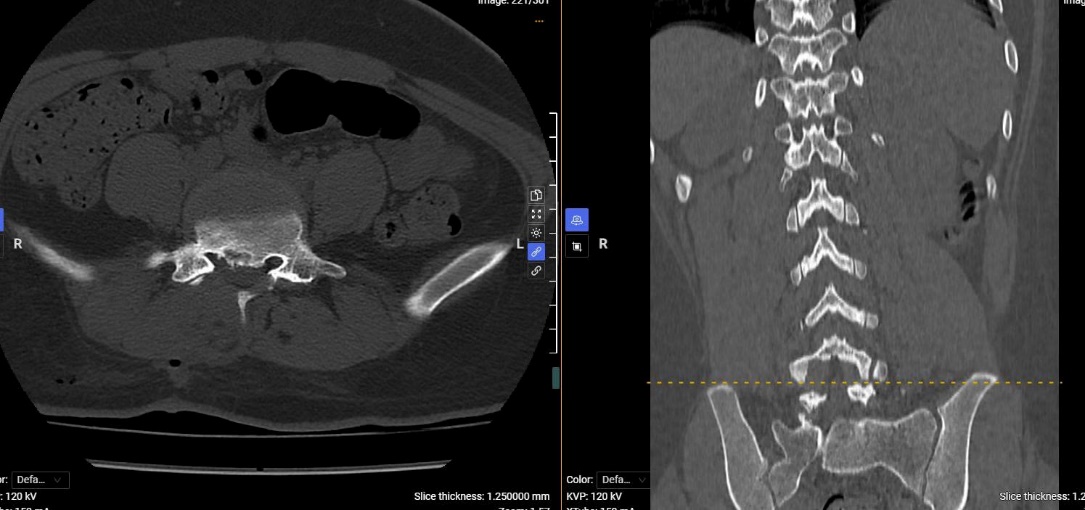

Hình ảnh phim chụp CT của người bệnh sau phẫu thuật